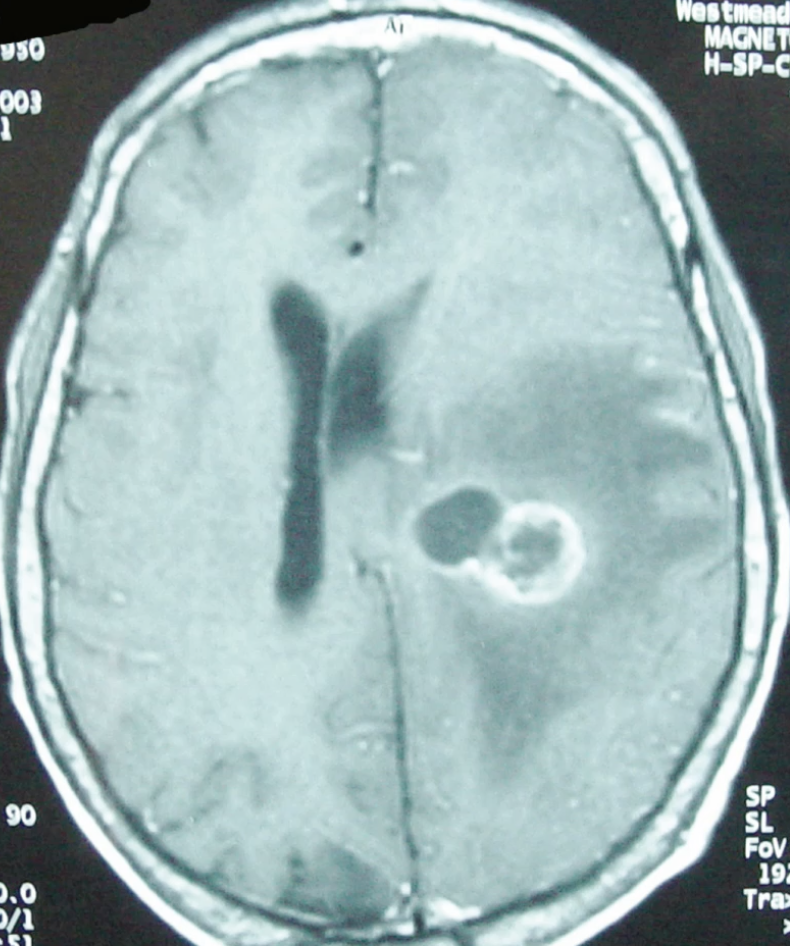

Nocardia - Branching gram positive rod (aerobic)